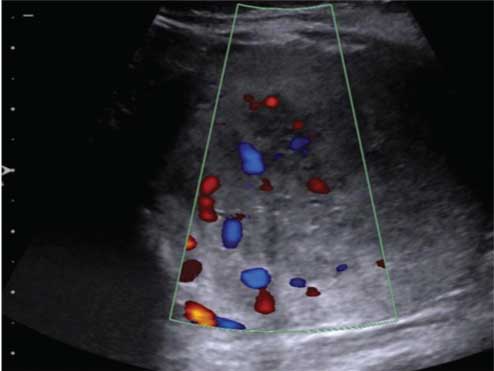

USG of the swellings at the nape of neck and the dorsolumbar region demonstrated ill-defined margins with increased internal echogenicity, consistent with lipomatous nature, without any vascularity or cystic content. On abdomen-pelvic sonography, a well-defined heterogeneously hypoechoic solid mass of size 4.7 cm (AP) × 6 cm (TR) × 4.4 cm (CC) was detected in the lower abdomen and pelvis [Table/Fig-2a]. The mass was separate from the uterus and adnexa and demonstrated central vascularity on colour Doppler [Table/Fig-2b]. Non-Contrast CT abdomen to evaluate the mass showed it to be retroperitoneal, relatively well marginated, solid, extending from left lower abdomen into the pelvis with displacement of bowel loops to the right and anteriorly.

A well marginated echogenic solid mass with small cystic areas seen in the mid lower abdomen, extending to the pelvis, but not arising from the uterus, adnexa or bladder.

Colour Doppler images shows significant vascularity within the mass.